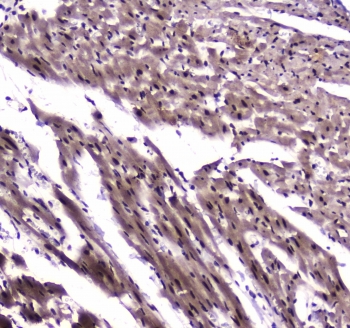

IHC testing of FFPE rat heart tissue with NFIB antibody at 1ug/ml. Required HIER: steam section in pH6 citrate buffer for 20 min and allow to cool prior to staining.